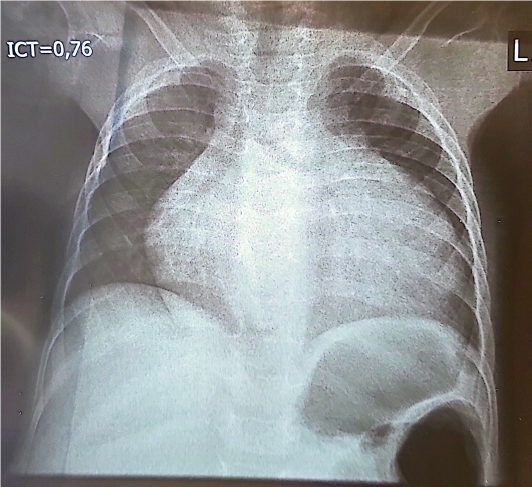

Il y avait une cardiomégalie (figure 2) avec un Index Cardio Thoracique (ICT) à 0,76, sans présence de troubles ventilatoires.

Figure 2 : Radiographie pulmonaire de face, chez un enfant de 10 mois,

porteur de maladie de la Pompe infantile et d’un albinisme

oculo-cutané, montrant une cardiomégalie avec ICT à 0,76